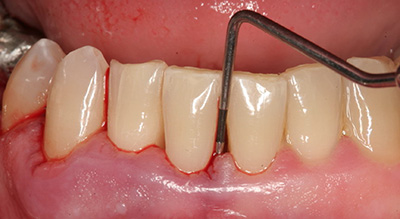

Обязательно измеряют глубину зазора между десной и зубом. Такая несложная процедура помогает определить масштаб поражения. Для этого применяют пародонтальную пробу, которая помещается между зубом и десной. Таким способом обследуют каждый зуб, а совокупность результатов даёт пародонтограмму.